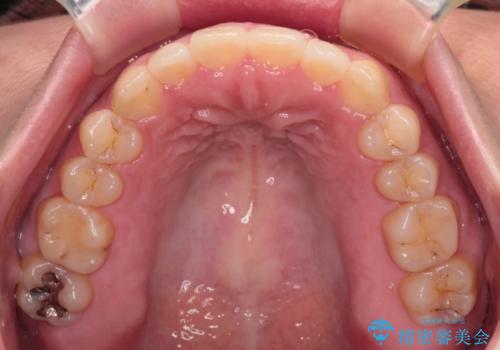

【モニター】カリエール・ディスタライザーを併用した八重歯のインビザライン矯正

- 前歯の叢生と八重歯を気にして来院された患者様です。

目立たない装置を希望とのことで、インビザラインにて矯正治療を行うこととしました。

インビザライン単体で改善することも可能ですが、八重歯とその後方にある歯列を確実移動させないと、上下正中がずれてしまう可能性があります。

インビザライン単体での治療ではなく、カリエール・ディスタライザーという補助装置を併用して、より確実性を上げることとしました。

補助装置で八重歯を解消しながら、並行してインビザラインで歯列を整えることとしました。

カリエールディスタライザーを併用したことで、すっきりとした口元になり、上下の正中を合わせることができました。